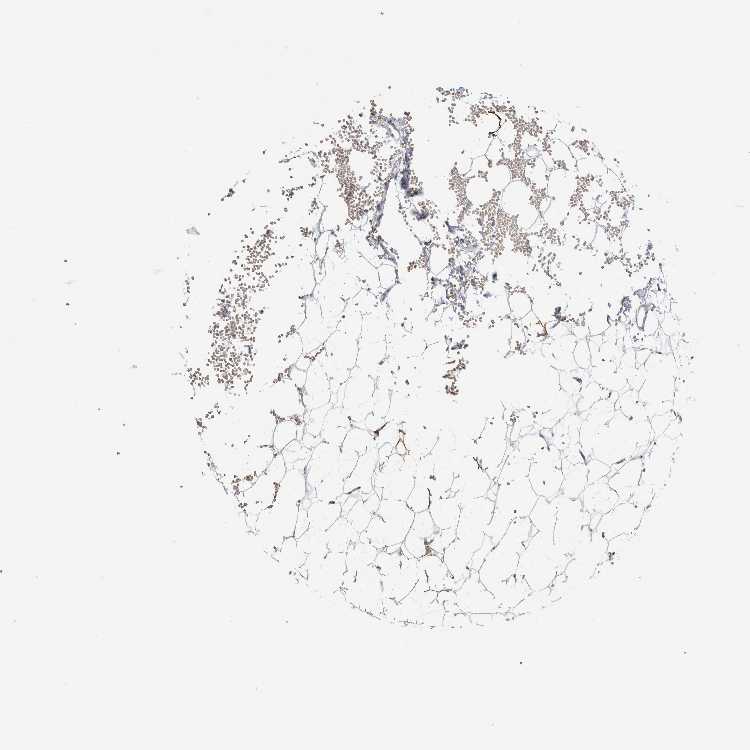

SOFT TISSUE 1 - Antibody stainingi

Antibody staining in the annotated cell types in the current human tissue is reported as not detected, low, medium, or high, based on conventional immunohistochemistry profiling in selected tissues. This score is based on the combination of the staining intensity and fraction of stained cells.

Each image is clickable and will lead to virtual microscopy that enables deeper exploration of all samples and also displays staining intensity scores, fraction scores and subcellular localization as well as patient and tissue information for each sample.

Antibody HPA011284Antibody CAB026403

Chondrocytes -Not detected

Fibroblasts Not detectedNot detected

Peripheral nerve Not detected-